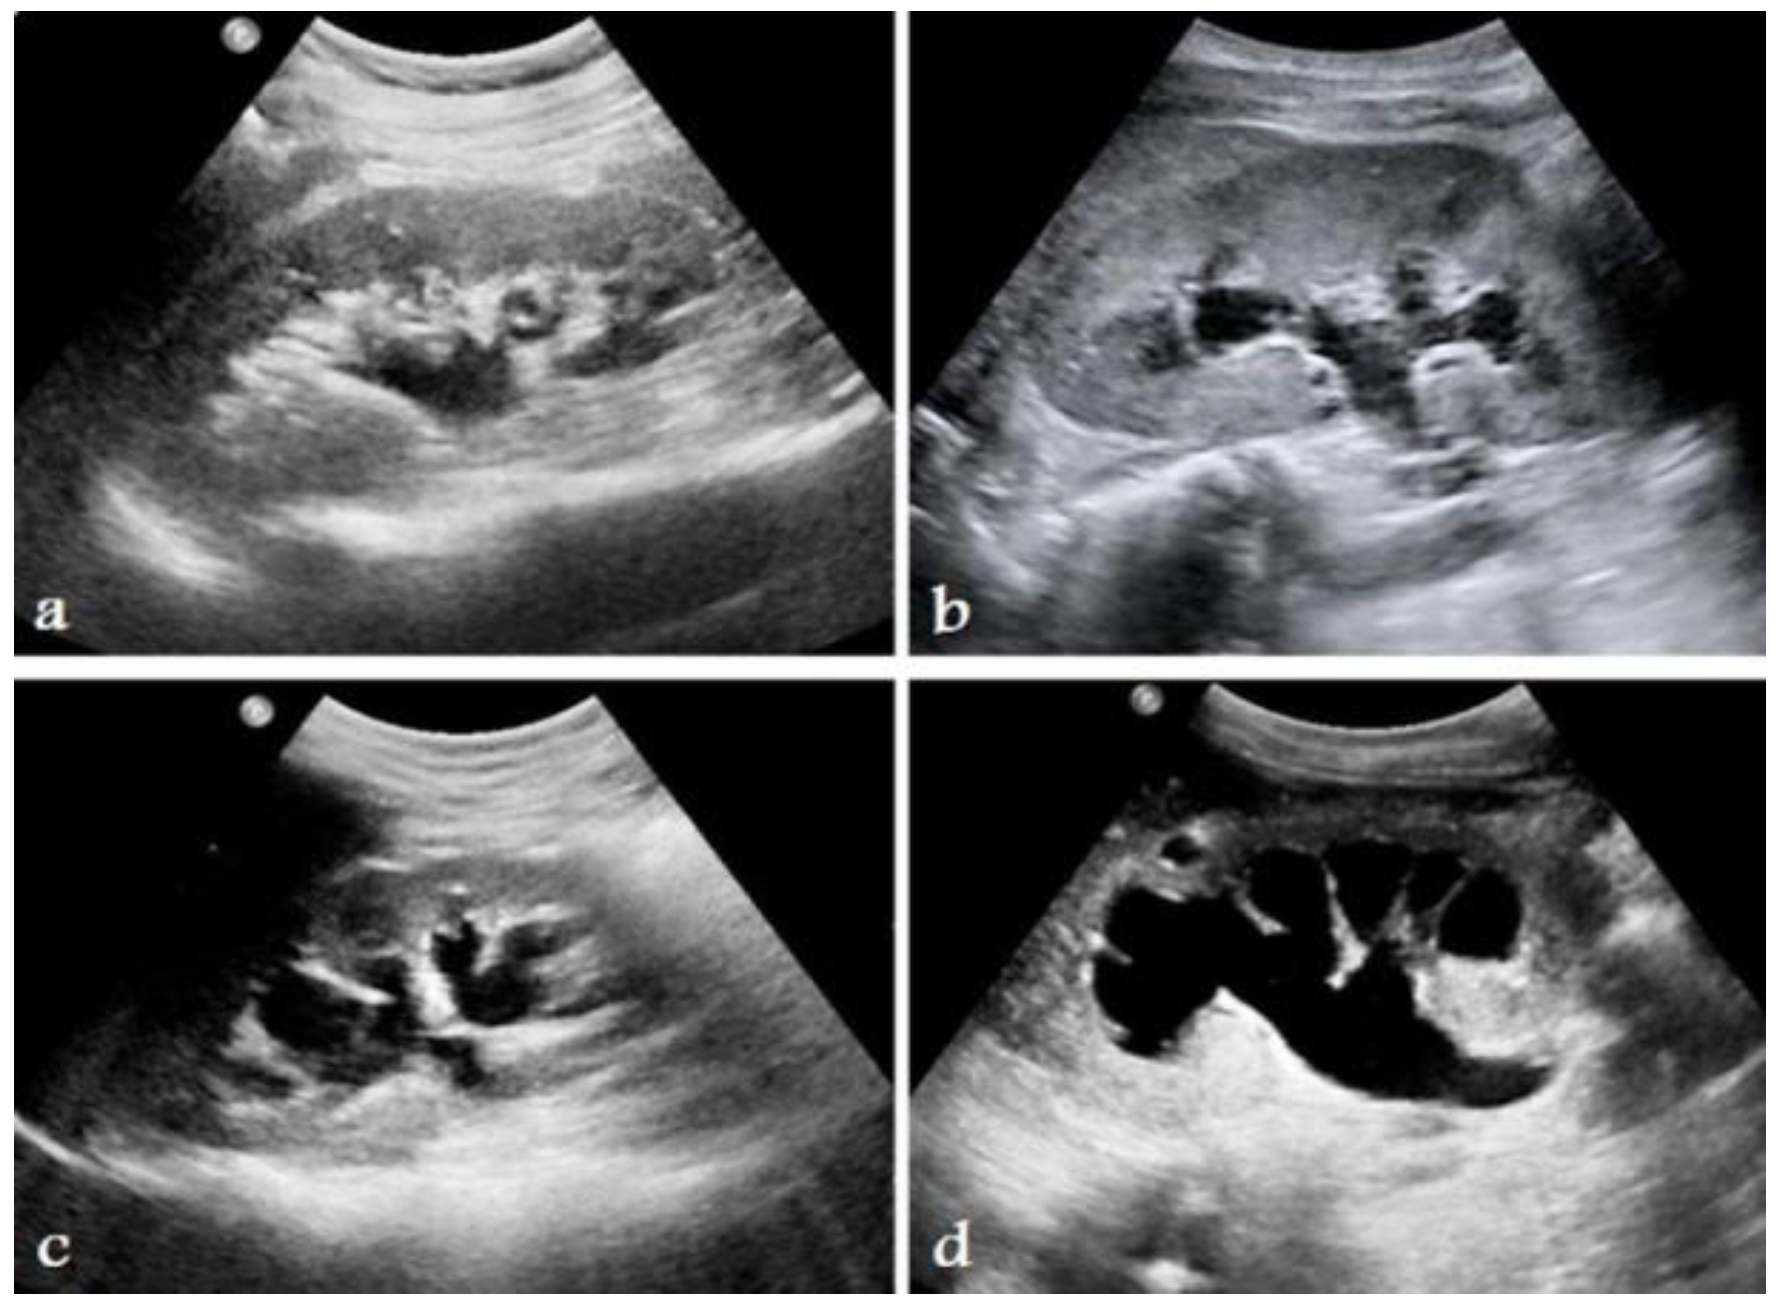

- Imaging modalities: A number of imaging modalities, such as intravenous pyelography (IVP), CT, MRI, and ultrasound, are essential for the diagnosis of juvenile kidney cancers and stones. Ultrasound is noninvasive and emits no ionizing radiation, so this method is used as a first-line imaging modality to examine renal morphology and identify structural problems (Figure 6). CT and MRI are more sensitive and specific for assessing stone load and identifying renal masses but also entail radiation exposure and require patient sedation [40].

- Improved diagnostics: AI-driven image analysis tools can enhance the identification and description of pediatric kidney cancers and tumors. Radiologists can spot minor abnormalities, characterize renal masses, and estimate tumor burden more accurately using ML algorithms that have been trained on large datasets of pediatric renal images (Figure 7). AI algorithms enable the early identification of kidney cancers and tumors by methods including pattern recognition, masking, segmentation, and quantitative analysis, allowing for confident diagnosis and timely treatment [24].